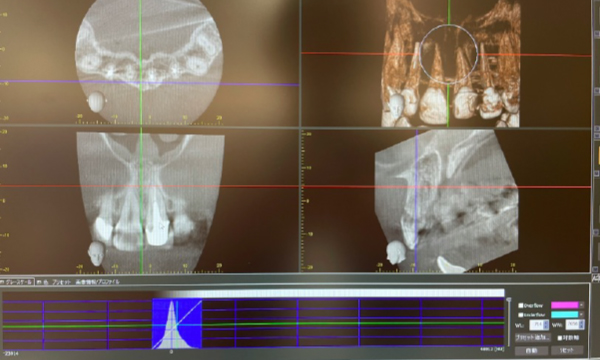

ですが現在はCT撮影が可能になり、得られる情報量が飛躍的に増えて、より正確な診断と治療が可能になりました。

近年、根管治療のためのCT撮影が保険で算定可能になりました。(約3,500円)

CTは主に抜歯やインプラントなどの外科処置根管治療で使います。

当院はCTを完備していますので、撮影後すぐに診断・治療が行えます。

- 1.CTで精密な診査

1.CT(3Dレントゲン)でわかること

根管の形態は一人一人異なり、枝分かれ・狭窄・湾曲などしていることもあるため非常に複雑です。さらに直接見ることもできません。

今まではその複雑な形態を把握する手段が、二次元のレントゲン撮影しかなかったため、いろんな角度で撮影するなどして対応してきました。